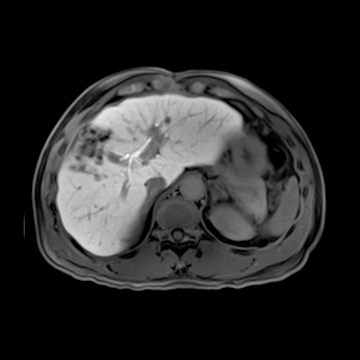

腹部造影検査

MRI画像(提供:シーメンスジャパン株式会社)